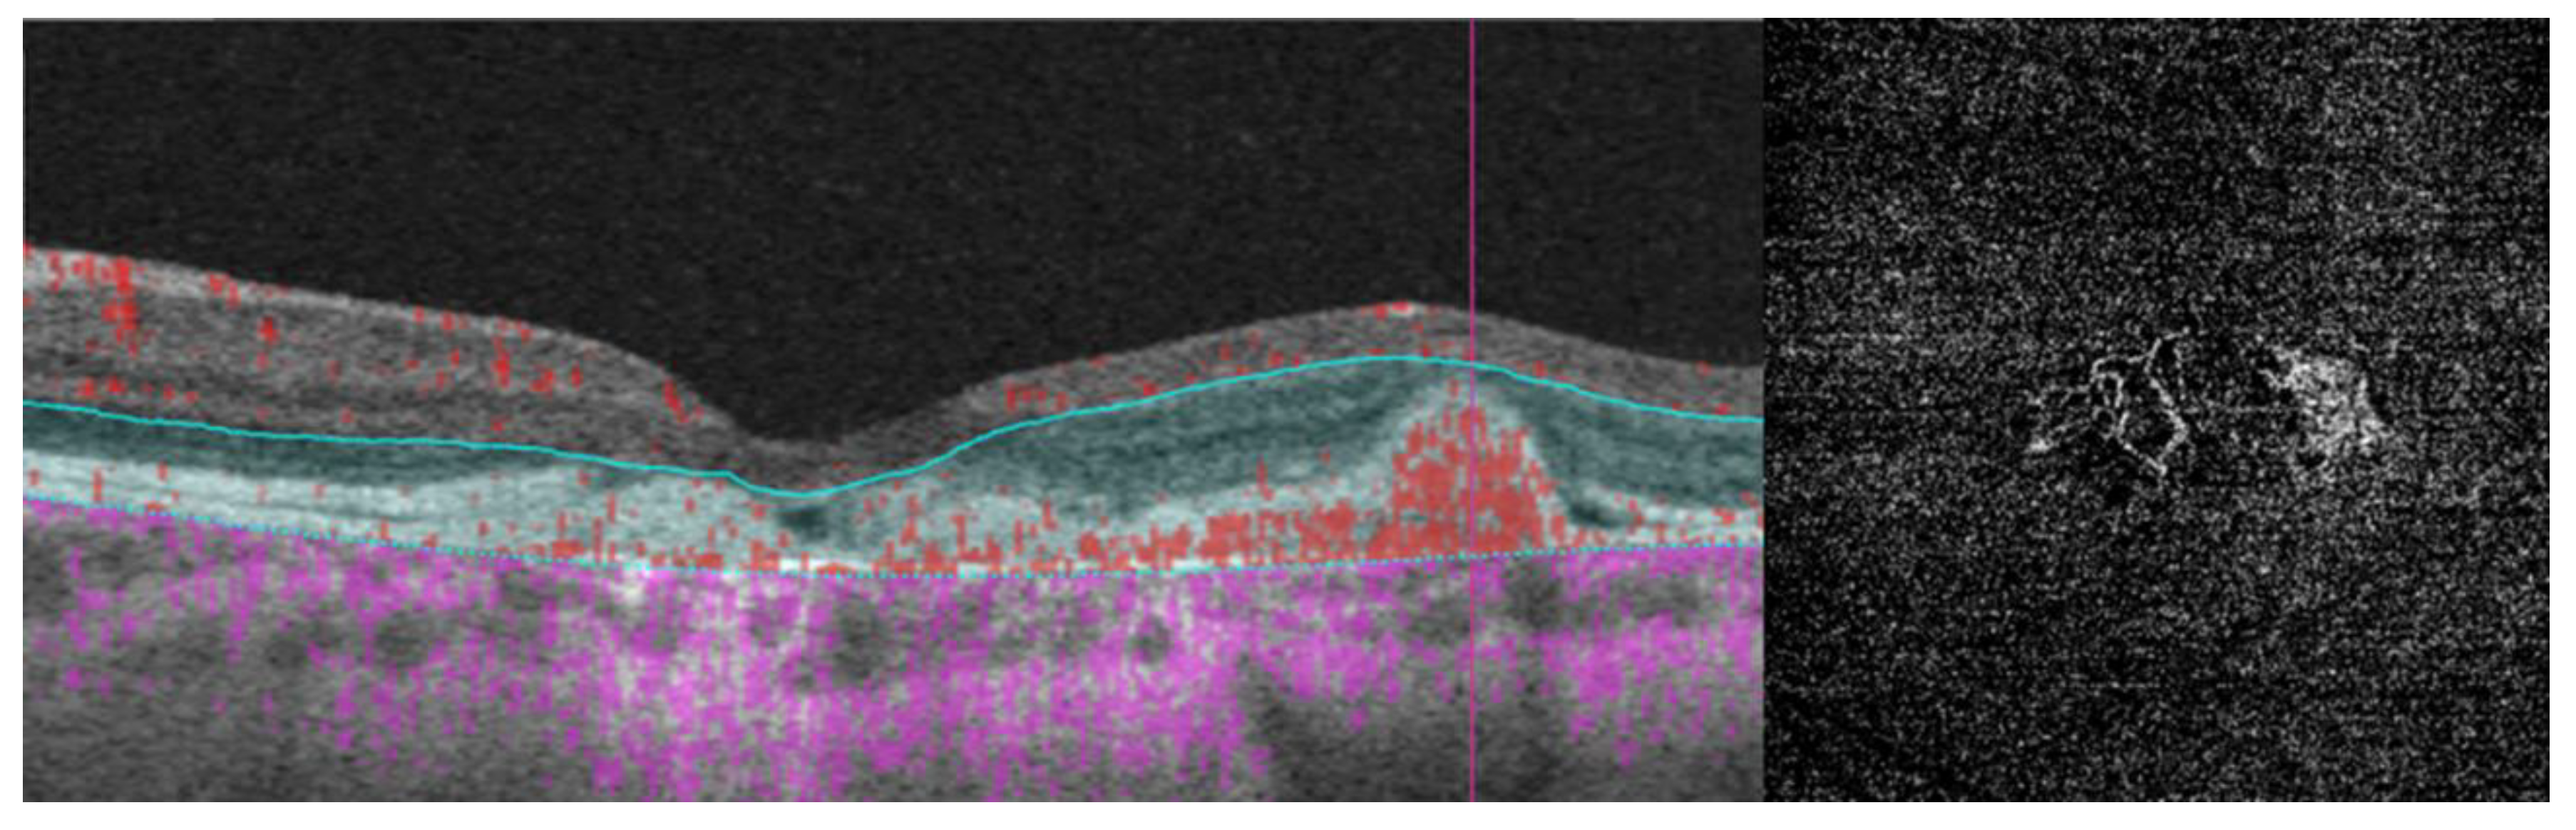

- The integrity of the EZ is the most closely linked factor to a decline in visual acuity. Its intensity, both in the affected areas and the surrounding regions, is attenuated in patients who show disease progression, and expansion of the disrupted EZ region is linked to a higher probability of visual acuity loss. Additionally, it is worth noting that many patients exhibit a central region with a preserved EZ, referred to as an optically preserved islet or OPI, which is associated with improved visual outcomes [29]. However, it is essential to recognize that EZ loss tends to occur in later stages and is typically associated with already significant visual impairment.

- Another noteworthy OCT biomarker is the measurement of ONL thickness, which can serve as an indicator of early photoreceptor degeneration. Irrespective of the clinical stage, BVMD patients exhibit reduced ONL thickness compared to healthy individuals [30]. Also, there is a correlation between ONL thickness and both BCVA and retinal sensitivity. Therefore, ONL thickness could prove to be a more valuable quantitative measure for assessing the anatomical loss of photoreceptors and the decline in macular function.

- Visual acuity is directly impacted by the presence of both vitelliform material and subretinal fluid. Eyes exhibiting vitelliform material typically demonstrate superior visual function, while the gradual reabsorption of this material, accompanied by the detection of subretinal fluid, is associated with a decline in visual acuity. Additionally, sensitivity, as measured by microperimetry, declines as vitelliform material is reabsorbed and subretinal fluid accumulates [31].

- Retinal hyperreflective foci (HRF) are punctiform lesions, typically smaller than 30 μm, primarily located in the outer nuclear and plexiform layers of the neuroretina. Battaglia Parodi et al. identified the presence of HRF in BVMD and noted an increase in their number as the disease progressed [32]. HRF may constitute accumulations of microglia or RPE cells detached from Bruch’s membrane (BM) and migrated into the subretinal space, eventually reaching the neuroretina [33]. Recent data obtained using polarization-sensitive OCT, which provides tissue-specific contrast, has lent support to the theory by demonstrating the presence of RPE cells within the vitelliform material and the neuroretina. Consequently, HRF appears to reflect the progression of the disease and may serve as a valuable biomarker for monitoring BVMD.

| Best vitelliform macular dystrophy |